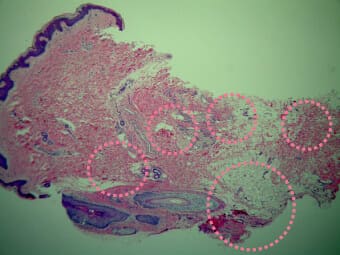

ミラドライは、厳格な臨床試験及び病理学的研究結果に基づき、厚生労働省や米国の政府機関であるFDA(食品医薬品局)の承認を受けた医療機器です。

わきにはエクリン汗腺とアポクリン汗腺という2種類の汗腺があり、これらが汗ジミやワキガの原因となります。ミラドライはこれらの汗腺にマイクロウェーブ(電磁波)を照射し、汗腺を破壊して機能をなくしていきます。失われた汗腺は再生せず、ワキガのニオイやわき汗を抑え半永久的な効果が期待できます。